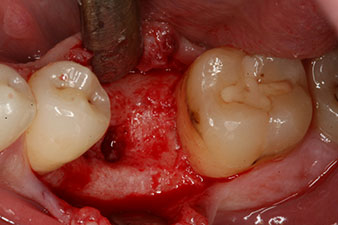

Fig. 2: Six weeks later there was an incompletely ossified alveolus in the region of the mesial root.

However, six weeks after the extraction incomplete ossification was found after preparation of the mucoperiosteal flap in the region of the former mesial alveolus.

Fig. 3: After preparation with the Implantmed implantology motor, an implant (diameter 4 mm, length 12 mm) was screwed in by the motor at a torque of 43 Ncm.

The implant was placed as planned after thorough removal of the granulation tissue (blueSky, bredent).